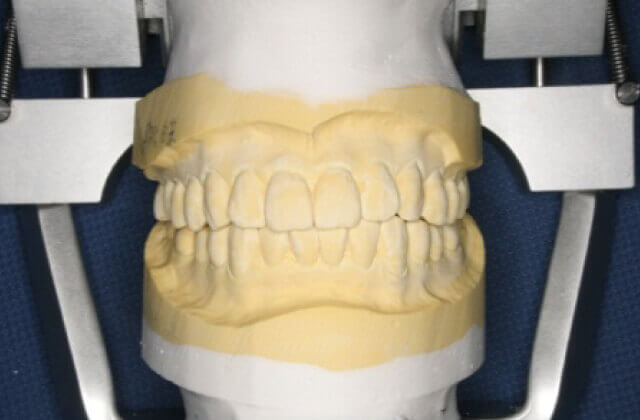

歯型を使った咬合器診査

かみ合わせ、噛み癖、歯の形などを診査します(現在のかみ合わせなどを再現します)